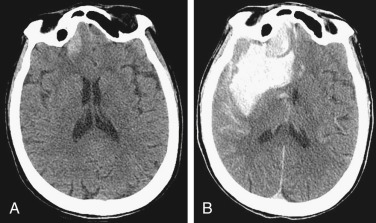

SDH

ICH